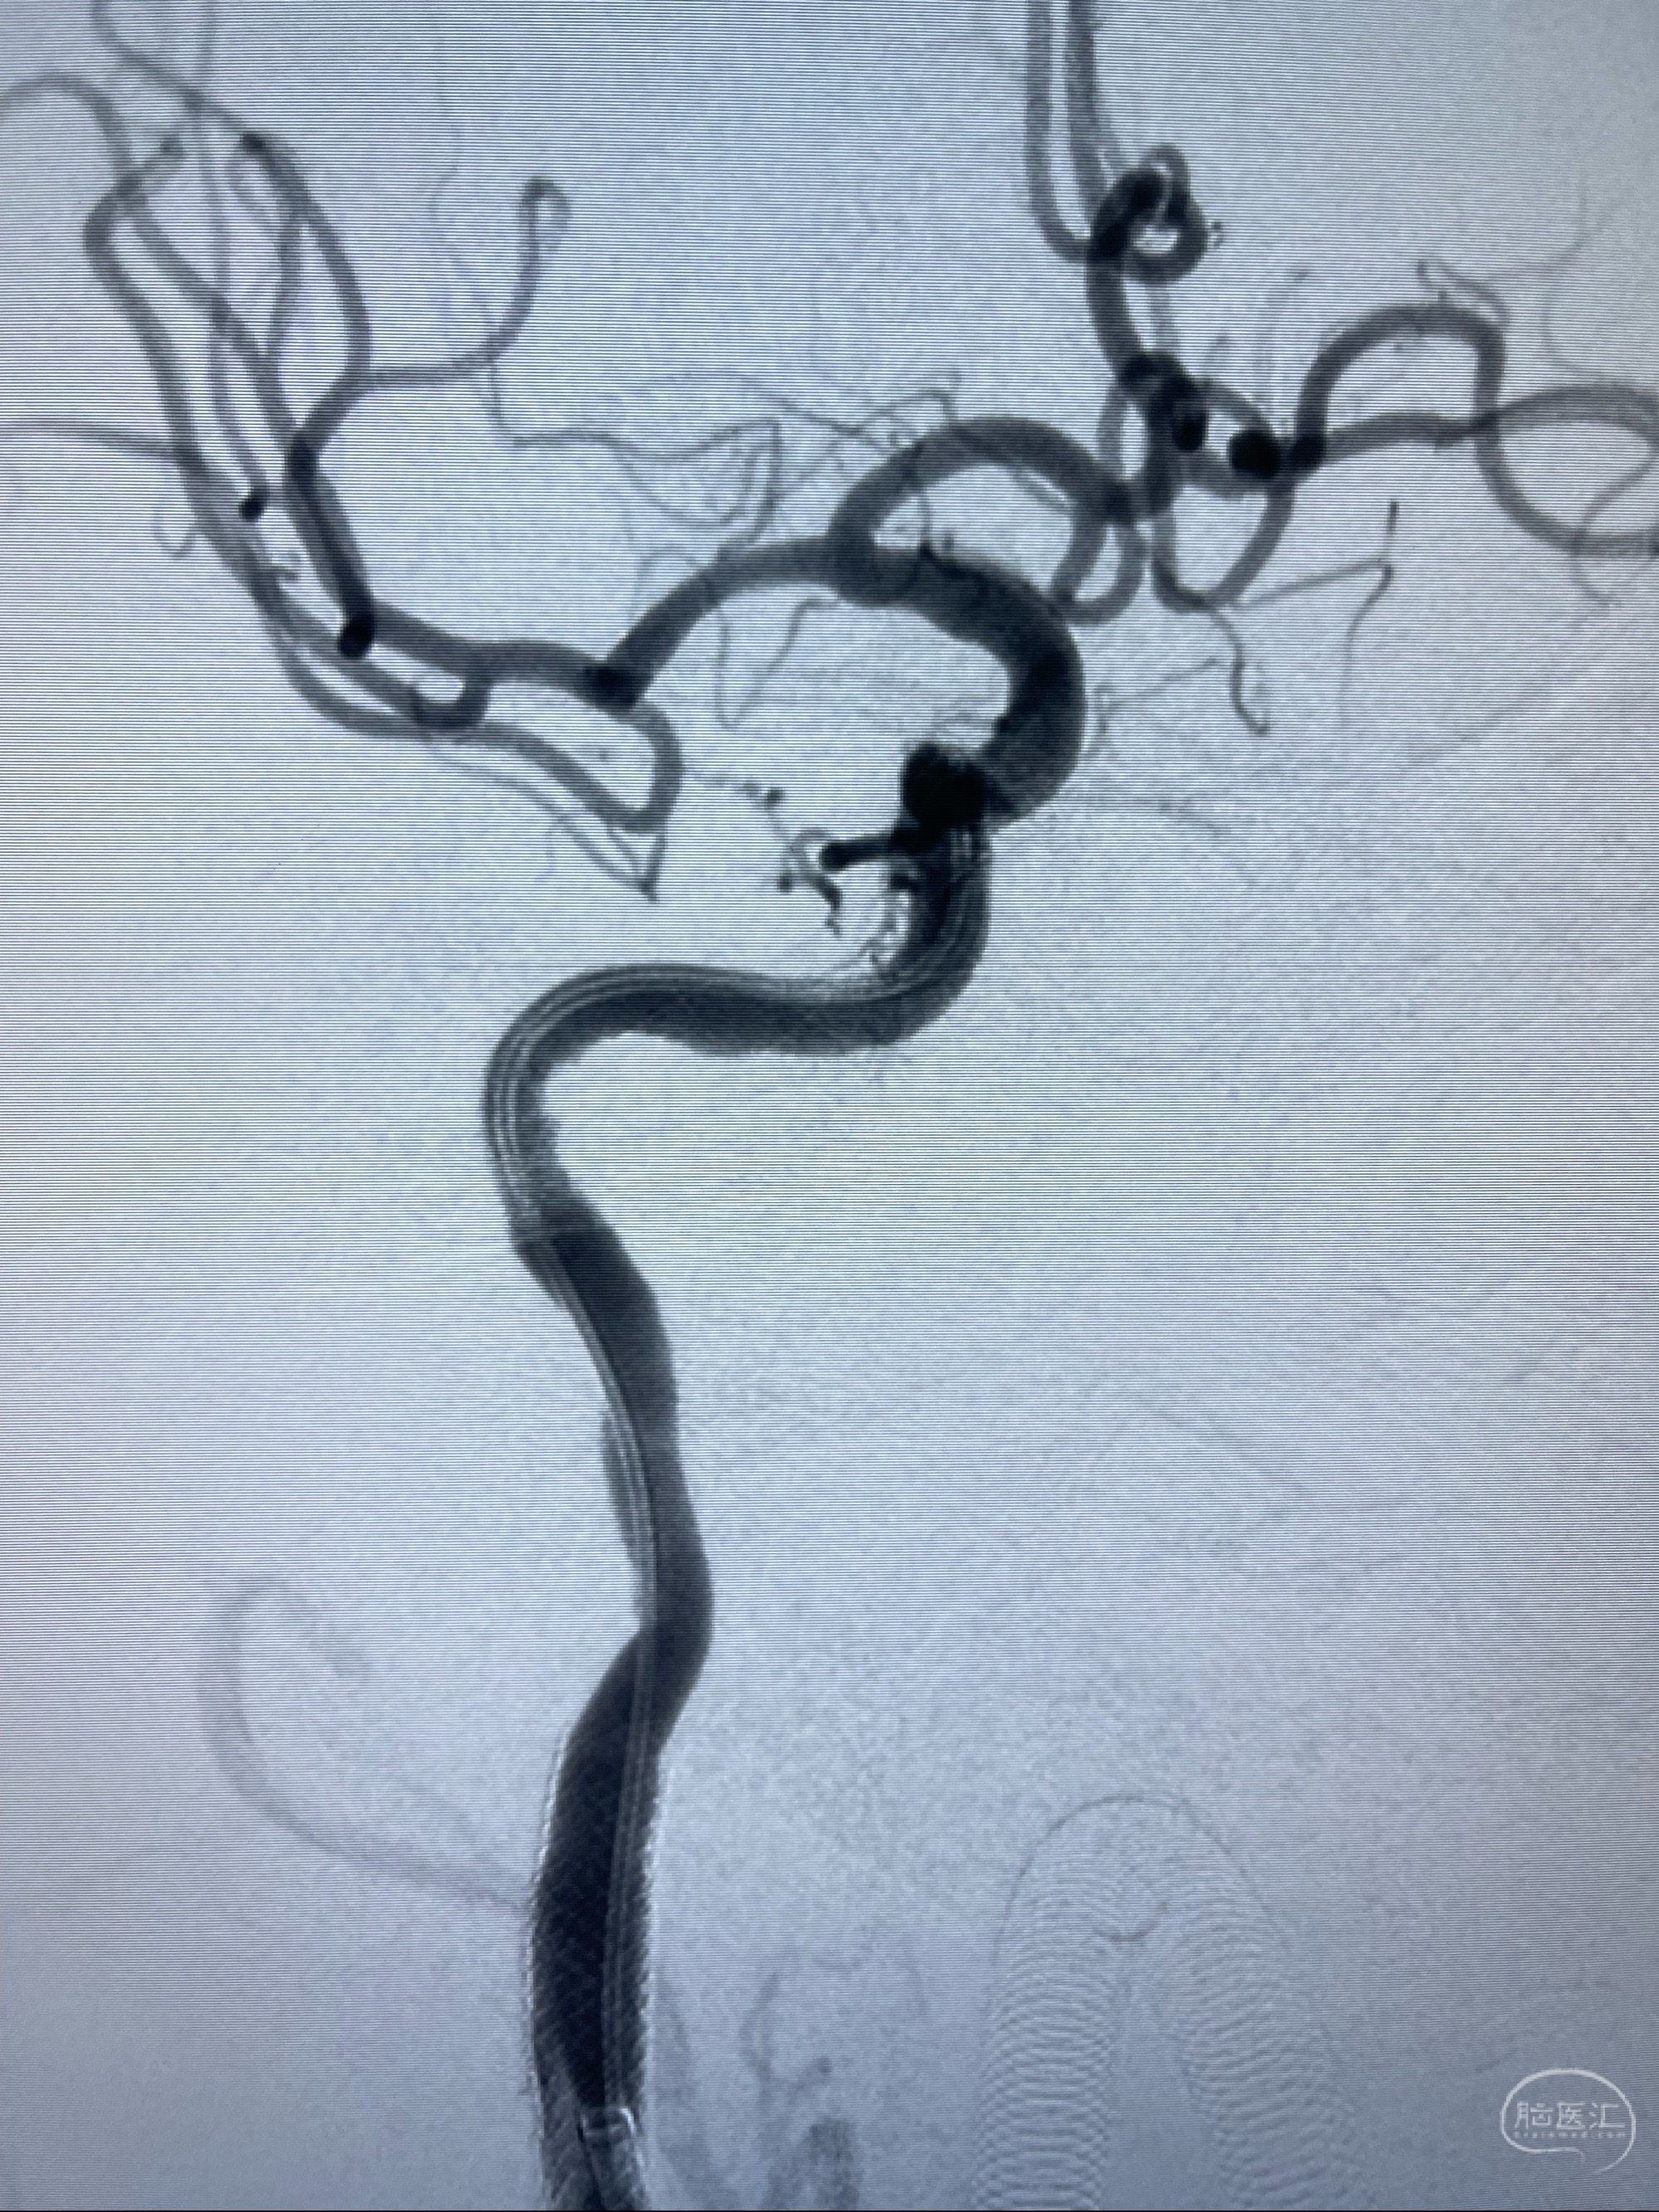

2023-07-10DSA:右侧颈内动脉岩骨段夹层伴中偏重度狭窄改变,左侧颈总动脉闭塞、右侧颈外动脉由右侧肋颈干甲颈干吻合代偿

箭头所示为颈内动脉岩骨段重度狭窄,结合MRI,考虑为肿瘤侵犯右侧颈内动脉

箭头以近至支架段管腔不规则狭窄

右侧椎动脉可见吻合代偿右侧颈外动脉

左侧颈总动脉起始段至分叉部闭塞,起始部呈现子弹头样改变

左侧椎动脉可见代偿显示左侧前循环

MRI:显示肿瘤侵犯右侧颈内动脉岩骨段上下,向下至原颈内动脉支架远心段,向上至颅底